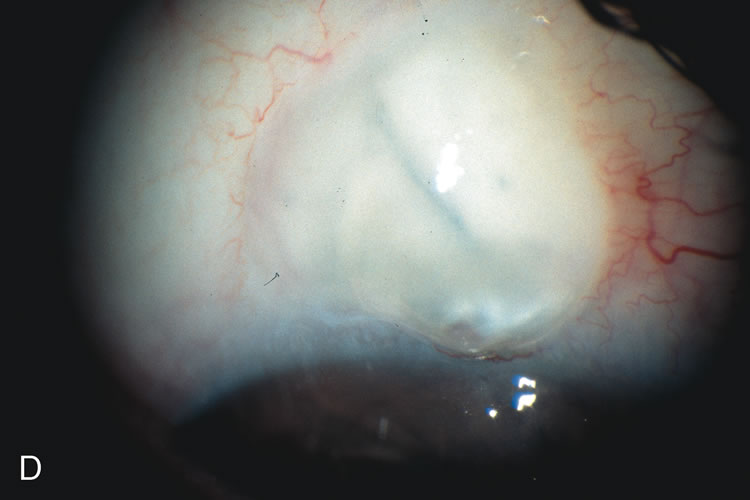

Cataract extraction by any technique performed in a patient with a pre-existing filter will have an effect on the previous filtering bleb.121–124 Bleb failure is more likely with ECCE compared with small-incision phacoemulsification.125 However, even patients undergoing topical anesthesia with clear corneal phacoemulsification and foldable IOL may experience bleb failure. One of three patients with a functioning filter and preoperative mean IOP of 12 mm Hg without antiglaucoma medications experiences bleb failure after lens extraction (Table 2). These patients require long-term drug therapy or bleb needling to control IOP. 126 Additional incisional glaucoma surgery may eventually be required in up to 10% of patients.127 Intraoperative iris manipulation may cause significant breakdown of the blood–aqueous barrier, resulting in inflammation that causes bleb failure. Even after uncomplicated clear corneal phacoemulsification, IOP may increase an average of 2 to 3 mm Hg due to bleb fibrosis.128 Approximately 20% of filtered patients require a long-term increase in glaucoma medications following uncomplicated clear corneal phacoemulsification with a foldable copolymer acrylic IOL129 (Fig. 3). In situations in which the bleb is not working at all, the eye will have a postoperative pressure spike that mimics that in the patient not having had a prior filtering procedure. In situations in which the bleb is marginal, the pressure spikes tend to be lower, and the final postoperative IOP tends to be around 50% higher than it was preoperatively. These patients require combined procedures in order to reestablish long-term filtration. In situations in which the bleb is very thin, polycystic, and associated with an IOP around 5 to 8 mm Hg on no antiglaucoma therapy; uncomplicated cataract extraction will have a minimal effect on the level of IOP. Patients with functioning glaucoma drainage implants usually have minimal long-term changes in IOP after uncomplicated cataract extraction.130

Fig. 3. Partial bleb failure following clear corneal phacoemulsification with foldable IOL. A. Preoperative bleb appearance prior to temporal lens extraction. Preoperative IOP was 12 mm Hg on no antiglaucoma medications. Time from 5-FU trabeculectomy surgery to lens extraction was one year. B. Bleb appearance 2 months after clear corneal cataract surgery with topical anesthesia. Following lens extraction, increased vascularity was noted along with decreased size of the filtering bleb. IOP increased to 20 mm Hg as early as 2 weeks after surgery, necessitating topical antiglaucoma therapy. C. High magnification view of bleb before lens extraction demonstrates diffuse pale bleb. D. High magnification view of bleb 2 months after surgery. There are vessels surrounding the nasal side of the bleb and the overall bleb size is smaller.